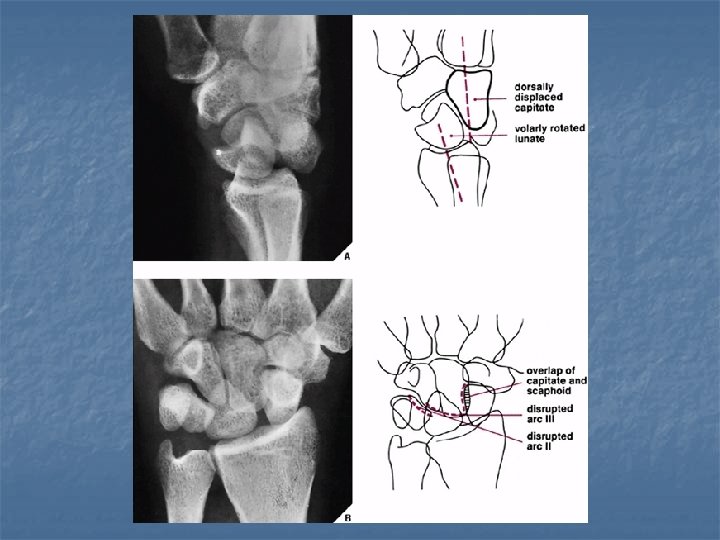

Perilunate dislocation n On lateral view: Dorsal or volar dislocation of the capitate. n Lunate remains in articulation with the radius although there may be some degree of tilt n n On dorsovolar view Crowdening of the proximal and distal carpal rows n Break in arcs II and III at the site of the capitate n

Lunate dislocation n On lateral view Axis of lunate is titled away from the articular surface of radius (spilled tea cup sign) n Capitate remains in normal alignment with radius and 3 rd metacarpal n n On dorsovolar view n Disruption of arc II while arc III remains intact